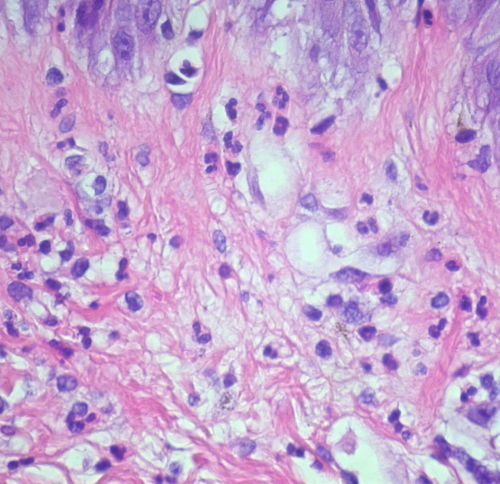

Exanthematous pustulosis = البثار الطفحي